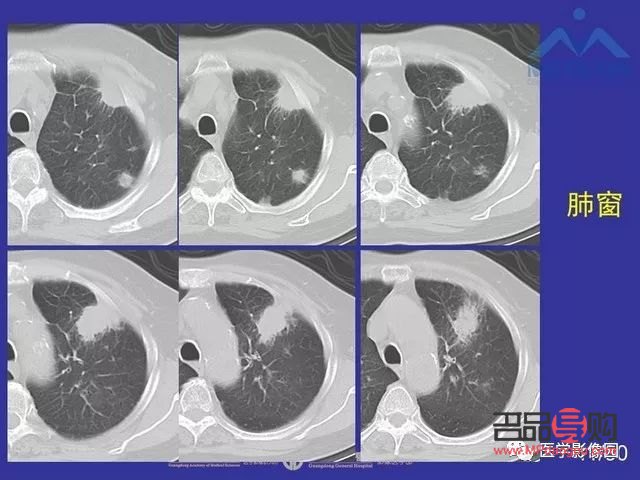

五、定期隨訪,密切關(guān)注病情變化

肺結(jié)節(jié)患者需要定期進(jìn)行肺部影像學(xué)檢查,以便及時(shí)發(fā)現(xiàn)病情變化,如有異常,應(yīng)及時(shí)就醫(yī),聽(tīng)從專業(yè)醫(yī)生的建議,進(jìn)行針對(duì)性的治療。